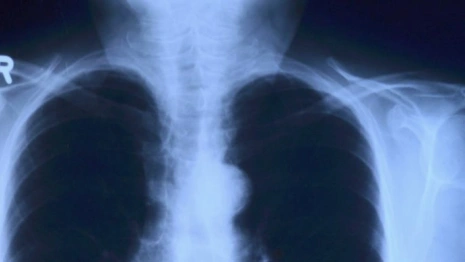

После рентгена выяснилось, что у мальчика было сломано плечо. Тогда родители написали заявление в полицию. Однако правоохранители в возбуждении уголовного дела отказали.